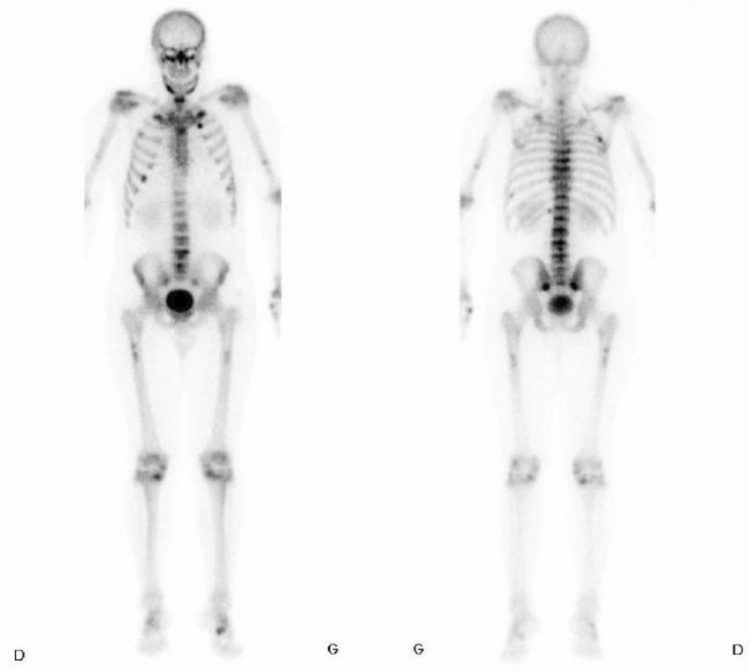

肿瘤诱导骨软化症(TIO)是一种罕见的获得性副肿瘤综合征,由间质肿瘤分泌一种名为FGF23的磷化激素引起。患者表现为骨痛、脆性骨折和肌肉无力。生化结果显示低磷血症,血清碱性磷酸酶升高,骨化三醇降低。我们报告一例44岁的男性,因急性腰痛到急诊室,显示D2和L5之间广泛的软骨下骨折。调查显示部分范可尼综合征;然而,他有严重的低磷血症,低1,25- oh维生素D和升高的FGF23水平提示诊断为肿瘤诱导的骨软化症。在范可尼综合征的背景下,最初通过PET-CT检查发现左腿皮下病变,以排除恶性肿瘤。肿瘤切除术使电解质紊乱在手术后几天内得到完全解决。本病例显示TIO可能表现为部分范可尼综合征,强调了在低磷血症病例中检测其他电解质的重要性,以及在部分范可尼伴严重低磷血症病例中寻找TIO的必要性。

Tumor-induced osteomalacia (TIO) is a rare acquired paraneoplastic syndrome caused by a mesenchymal tumor secreting a phosphaturic hormone called FGF23. Patients present with bone pain, fragility fractures and muscle weakness. Biochemical results show hypophosphatemia, raised serum alkaline phosphatase and reduced calcitriol. We report the case of a 44-year-old man who presented to the Emergency Departement with acute low back pain revealing extensive subchondral fractures between D2 and L5. Investigations showed partial Fanconi syndrome; nevertheless, he had profound hypophosphatemia, low 1,25-OH vitamin D and raised FGF23 levels suggesting a diagnosis of tumor-induced osteomalacia. A subcutaneous lesion was identified in the left leg on a PET-CT initially performed to rule out malignancy in the context of Fanconi syndrome. Tumorectomy enabled complete resolution of the electrolyte disturbances within days of surgery. This case shows that TIO may present as partial Fanconi syndrome, highlighting the importance of testing other electrolytes in cases of hypophosphatemia and the need to look for TIO in cases of partial Fanconi with severe hypophosphatemia.